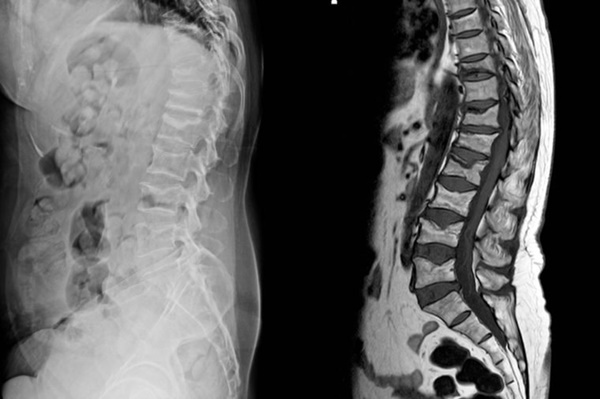

Nếu lưng bị tổn thương do tai nạn giao thông hoặc do va đập, bạn cần được kiểm tra y tế một cách toàn diện. Rất có thể bạn đã bị chấn thương cột sống hoặc một vấn đề nghiêm trọng nào đó. Chụp X-quang hoặc CT là những biện pháp kiểm tra giúp bác sĩ chẩn đoán chính xác tình trạng bạn đang gặp phải.

7. Bị loãng xương

Nếu bạn đã được xác định là bị loãng xương và cơn đau lưng thường đột ngột xuất hiện, rất có thể bạn đã bị gãy một đốt sống. Nguyên nhân phổ biến có thể do va chạm gần đây, nâng một vật nặng hoặc thậm chí do cơn ho dữ dội.

8. Cảm giác tê

Tổn thương tủy sống có thể dẫn đến tê liệt vĩnh viễn. Nếu bạn bị đau lưng và thường xuyên bị tê vùng chân, hãy đến bệnh viện để được kiểm tra. Nguyên nhân gây ra tình trạng này thường do chấn thương của một hoặc nhiều dây thần kinh vùng thắt lưng. Chấn thương các dây thần kinh có thể gây tê liệt hoàn toàn nếu chúng không được chăm sóc kịp thời.